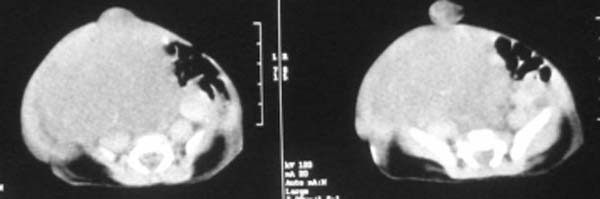

这个女孩刚出生一天,肚子比较大,没任何症状.比较少见,请大家积极发言!!

这个病例定位诊断:1、可以肯定肿块不在肝脏。2、肿块在腹膜后,因为肠管向前侧方推移,肾脏明显向后推挤,腹主动脉及下腔静脉被肿块包绕。

定性诊断比较困难,该病例肿块为实质性,小儿最常见的腹膜后肿瘤第一位应该是-----神经母细胞瘤!

我的意见是-----定位诊断是“1、可以肯定肿块不在肝脏。2、肿块在腹膜后,因为肠管向前侧方推移,肾脏明显向后推挤,腹主动脉及下腔静脉被肿块包绕。”

肝脏只是受推压改变,支持神经母细胞瘤

右中下腹部囊实性密度影,内有小细条状钙化影,胃及腹部肠管受压向左移位,肾脏受压向后移位,腹主动脉及下腔静脉包饶。考虑腹膜后畸胎瘤可能性大。